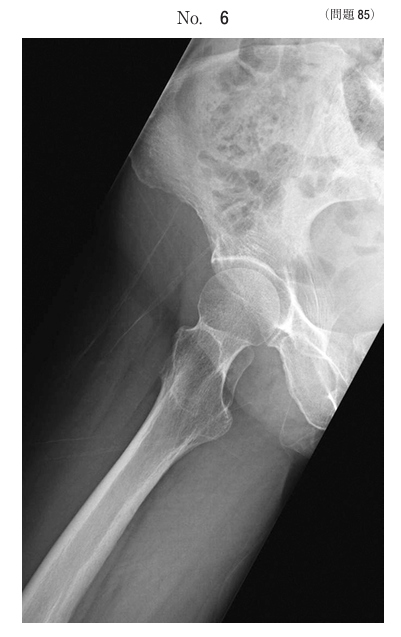

午前/問題85

X線写真別冊No. 6 を別に示す。撮影法で正しいのはどれか。

1.Martius(マルチウス)法

2.Stryker(ストライカー)法

3.Anthonsen(アントンセン)法

4.Caldwell(コールドウェル)法

5.Lauenstein(ラウエンシュタイン)法